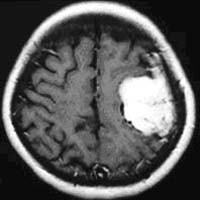

(2)脳動静脈奇形に対する液体塞栓物質を用いた治療

*治療により異常血管は閉塞されました。